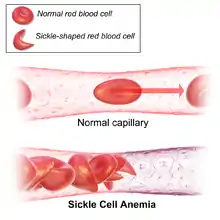

Resistance to malaria is a well-known example of recent human evolution. This disease attacks humans early in life. Thus humans who are resistant enjoy a higher chance of surviving and reproducing. While humans have evolved multiple defenses against malaria, sickle cell anemia—a condition in which red blood cells are deformed into sickle shapes, thereby restricting blood flow—is perhaps the best known. Sickle cell anemia makes it more difficult for the malarial parasite to infect red blood cells. This mechanism of defense against malaria emerged independently in Africa and in Pakistan and India. Within 4,000 years it has spread to 10–15% of the populations of these places.[80] Another mutation that enabled humans to resist malaria that is strongly favored by natural selection and has spread rapidly in Africa is the inability to synthesize the enzyme glucose-6-phosphate dehydrogenase, or G6PD.[15]